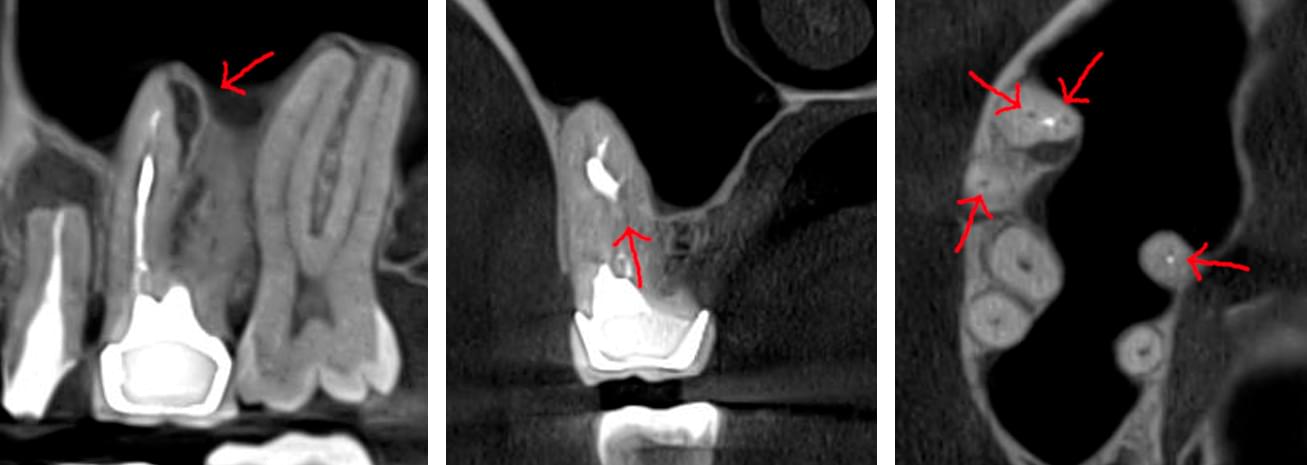

Коли коріння «ховає сюрпризи» - Корені зубів часто мають складну кривизну, гачкоподібні закручення або розгалуження, які на звичайному 2D-знімку накладаються один на одного, створюючи ілюзію прямого каналу. На плоскій картинці неможливо побачити реальний об'єм та напрямок вигину, що критично важливо при видаленні «зубів мудрості» або ендодонтичному лікуванні. КТ MyRay дає змогу лікарю заздалегідь побачити 3D-геометрію кожного кореня, оцінити його близькість до нижньощелепного нерва чи гайморової пазухи та підібрати правильну тактику роботи. Це мінімізує ризики поломки інструменту в каналі або травмування сусідніх структур, перетворюючи складну хірургію на прогнозовану процедуру.

При плануванні імплантації лікарю важливо знати дві речі: об'єм кістки та точне розташування нервів.

КТ дозволяє провести віртуальну операцію: встановити імплант у програмі, виключивши будь-які ризики травмування пацієнта.

Часто причиною зубного болю є гайморит, і навпаки — причиною запалення пазух є хворий зуб. На звичайному знімку пазуха виглядає як темна пляма. На КТ ми бачимо стан слизової, наявність кіст або сторонніх тіл (наприклад, залишків пломбувального матеріалу), що критично важливо для правильного діагнозу.